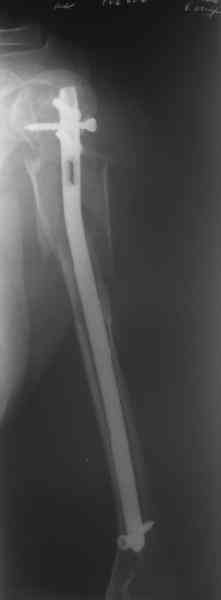

Здесь нет необходимости в серкляже. Вмешиваться на промежуточных отломках приходится, если есть угроза перфорации кожи, или промежуточный отломок попал в фасцию, как пуговица в петлю. В приложении сегментарный оскольчатый перелом плеча в проксимальном отделе, фиксированный больщеберцовым стержнем. Как видите, обошлось без серкляжа. Функция полная.

Александр, великолепные снимки! Вопрос - что за гвоздь?

Это укороченный большеберцовый стержень, которые делает предприятие "ЦИТО".

на синтезовский UTN похож))

Скажите пожалуйста, Александр Николаевич, почему Вы использовали большеберцовый гвоздь?

Доступные на тот момент гвозди для плеча имели худшие возможности фиксации в коротком проксимальном отломке.

Уважаемый Александр Николаевич! На продемонстрированных вами рентгенограммах имеется достаточно большое на мой взгляд смещение отломков после фиксации блокируемым гвоздем. На счет полной функции все понятно, а нет ли каких либо сосудистых расстройств конечности? Имею ввиду венозную недостаточность или лимфостаз.